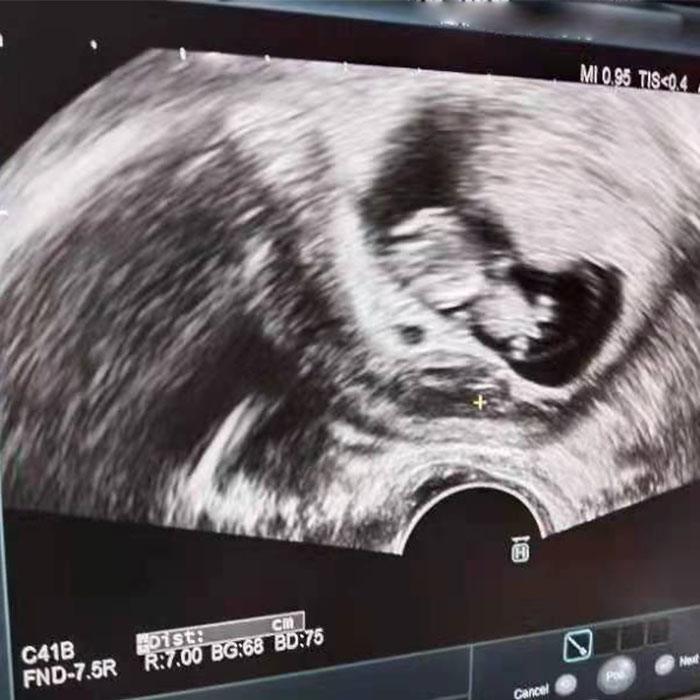

最終,楊女士移植了一枚男胚一次成功懷孕!